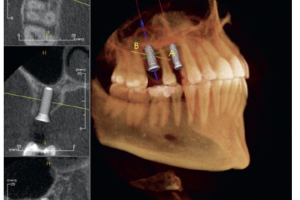

Радиационно-индуцированный некроз или остеорадионекроз характеризуется наличием обнаженной кости после проведения лучевой терапии. Открытая кость может полностью секвестрировать, что часто приводит к обнажению большего количества кости. Хотя кость, расположенная в любом месте челюсти, восприимчива к излучению, задняя часть нижней челюсти поражается чаще, чем другие области, потому что она часто находится в поле излучения, особенно когда в лечение включены лимфатические узлы. Может возникать интенсивная боль при периодическом отеке и дренировании вне полости рта. Однако многие пациенты не чувствуют боли при обнажении костей. Утрата нормальной структуры может нарушить целостность кости, а в некоторых случаях кость может сломаться.